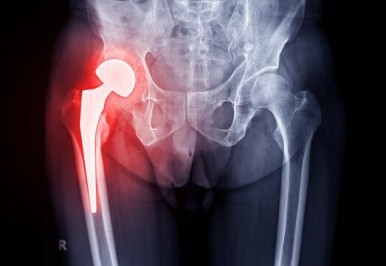

고관절(엉덩관절)은 골반과 대퇴골(넙다리뼈)이 연결되는 관절입니다.

고관절에 문제가 생기면 관절염, 고관절염증, 더불어 혈액순환의 문제, 골반틀어짐,

근육의 비정상적 단축 등 문제가 나타나겠지요.

움직임에 따라 고관절에 지속되는 통증이 있다거나 가동범위가 제한적이라면

염증이 나타나있을 확률이 있으니 병원에 방문하여 검진해보는것을 추천드립니다.